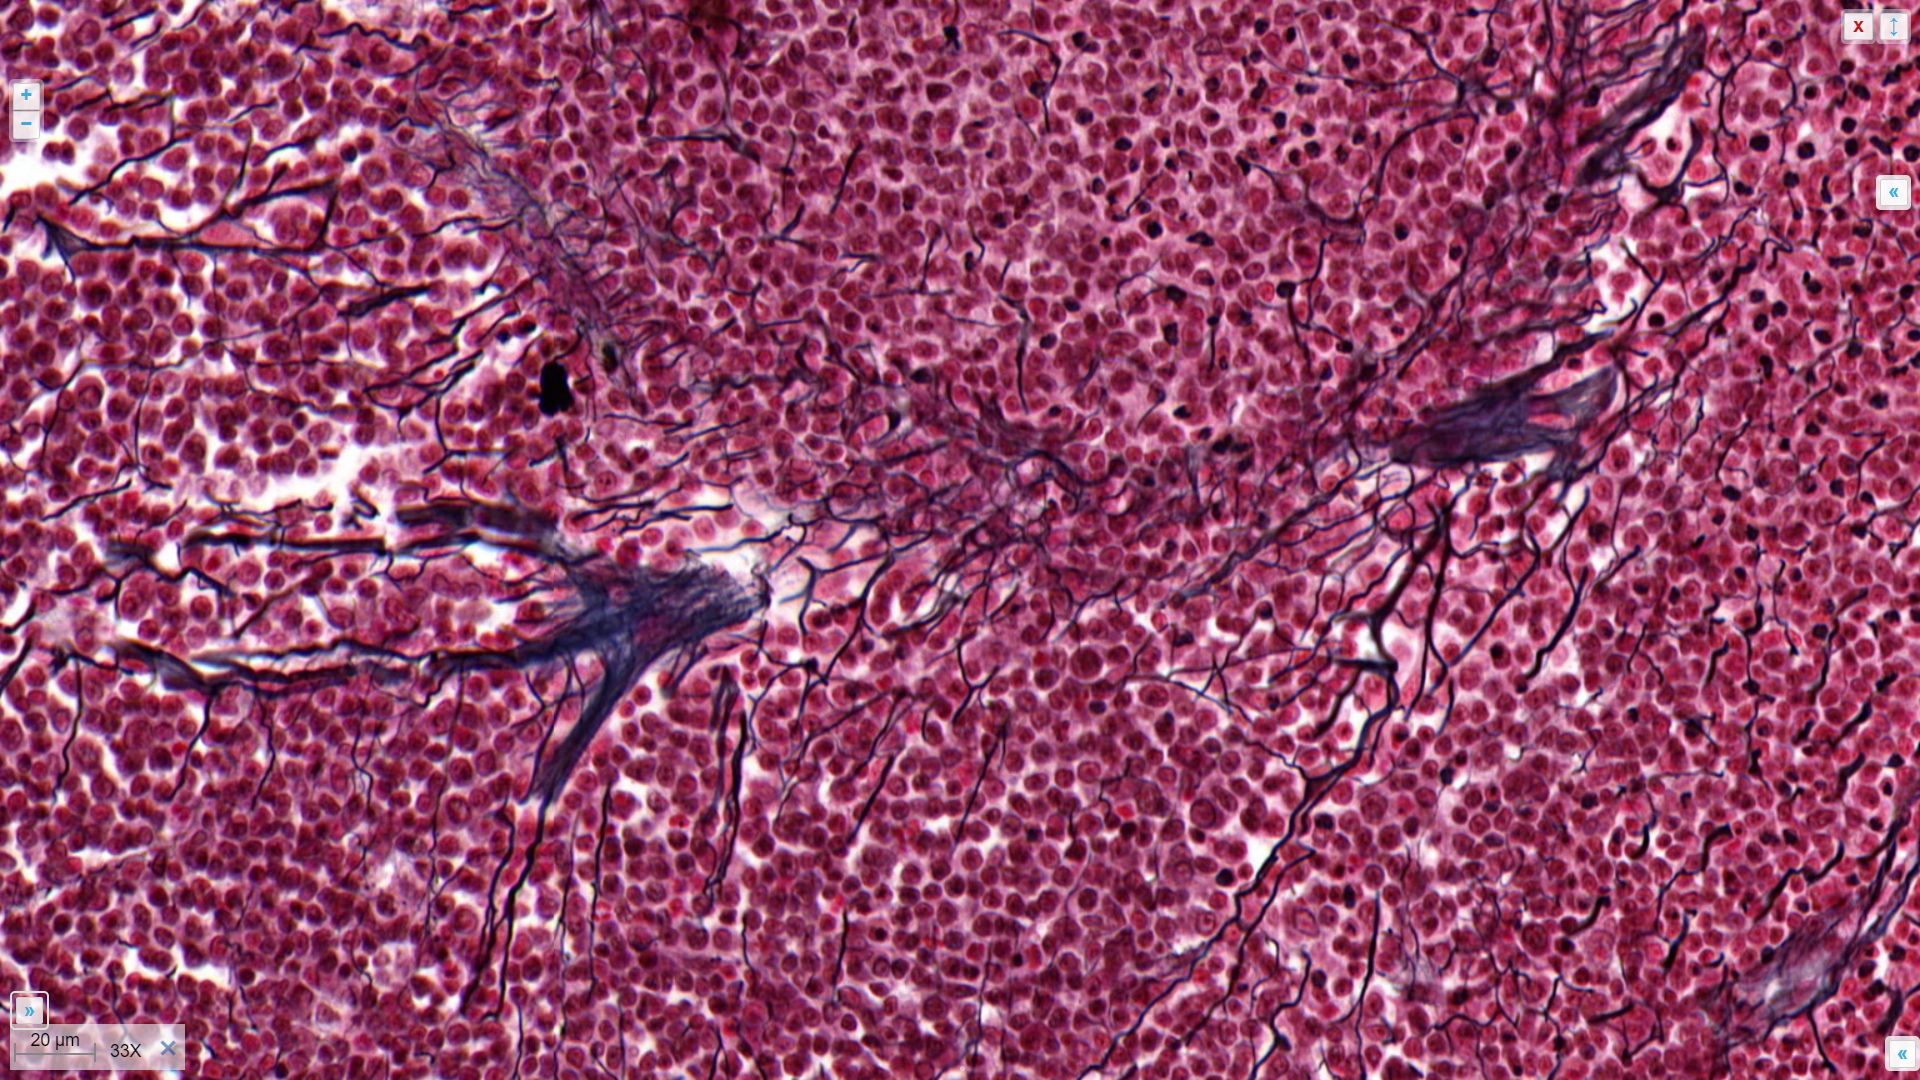

- Reticulair bindweefsel bevat een netwerk van vertakte cellen. De reticulumcellen (gespecialiseerde fibroblasten) maken reticulaire vezels ter ondersteuning van andere cellen. Deze andere cellen zijn bv. hematopoëtische (bloedvormende) cellen van het beenmerg of lymfoïde cellen van de lymfeklieren of milt.

Reticulair bindweefsel (zwart aangekleurd):